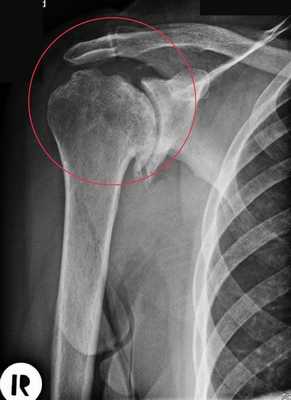

- остеонекроз - отмирание клеток головки кости;

- многооскольчатые сложные переломы и раскол головки;

- плохо сросшиеся старые переломы без возможности восстановления нормальной анатомии сустава;

- артрит;

Артроз плечевого сустава на рентгене.